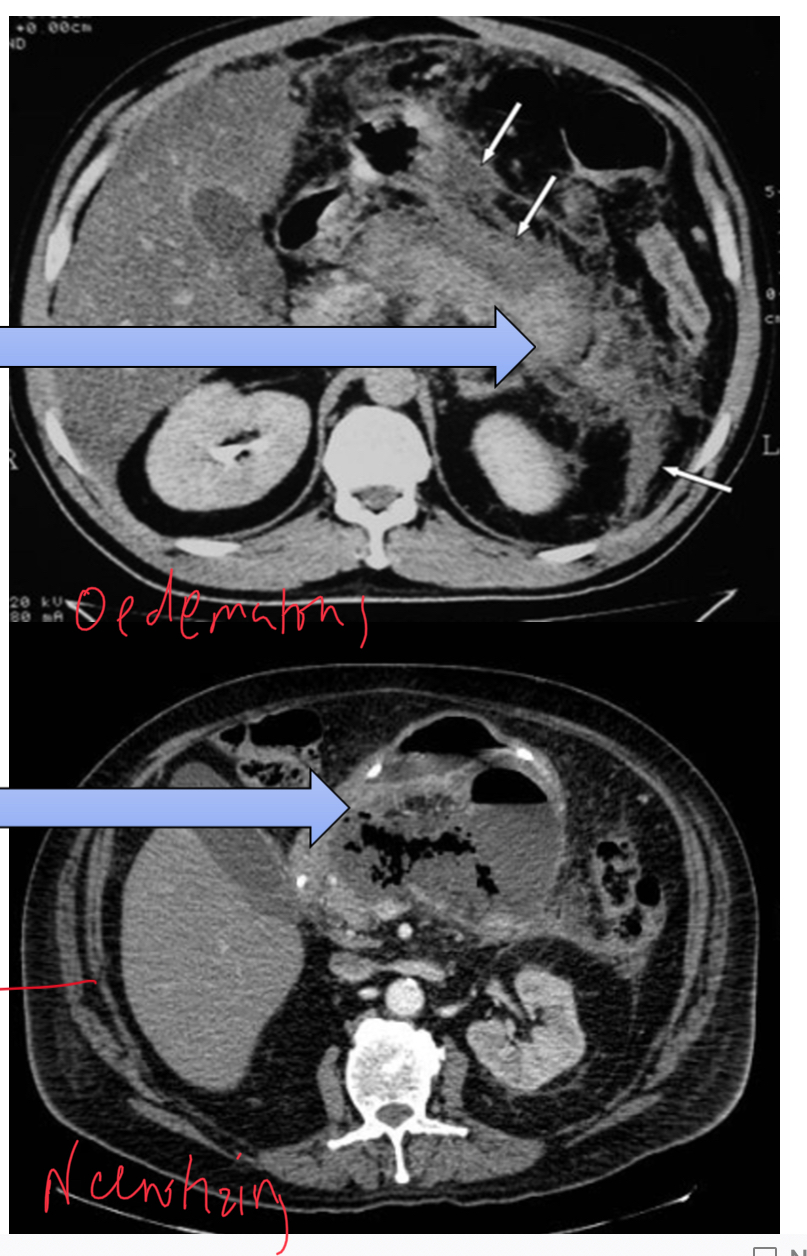

Oedematous pancreatitis

Hameorrhagic pancreatitis - caused by arroding of blood vessels

Necrotic pancreatitis - caused by infection which can lead to infective necrosis. Bacteria produce gas in pancreas.

not ideal: very hard to distinguish on scans which is which